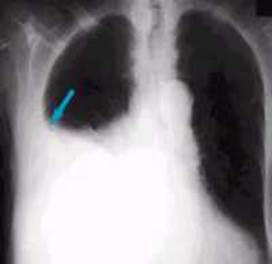

63 жасар әйелде кеуде клеткасы ағзаларының рентгенограммаларында сол жағында 5 қабырғаның алдыңғы кесіндісінде ашық түсті, тегіс(2 мм) сызық көрінеді, ол қабырғаны көлденеңінен кесіп өтеді, сызыққа дейінгі қабырғаның проксималды және дисталды кесінділері бір деңгейде орналасқан (ығысуы 3 мм дейін). Ауру сезімі мен дем алуының қиындағанына шағымданады, жарақат болмаған, саяжайда көп еңбек еткенін айтады. Осы рентгенологиялық сурет қай патологияға сай келеді:

A) Лоозерлік қайта құрылу аймағы

B) Қабырғасының сынуы

C) Өкпенің тамырлық суретінің қабаттасуы

D) Артефакт

E) Патологиялық сынық

{Дұрыс жауап}= B